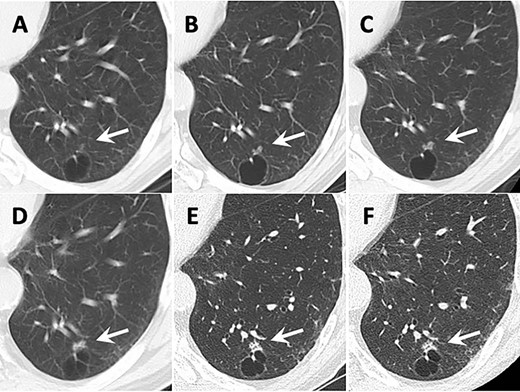

Transition of CT images. Arrows show the tumor. (A) 12 years before surgery. A small ground grass nodule (GGN) adjacent to the cyst wall was identified in the left lower lobe. (B) 9 years before surgery. (C) 6 years before surgery. The GGN showed enlargement. (D) 4 years before surgery. The GGN transformed to the solid lesion gradually. (E) 2 years before surgery. The small intralesional cavities were identified in the nodule. (F) The CT image taken just before surgery.

Twelve years before the surgery for CMPT, a 4-mm small ground grass nodule (GGN) was identified adjacent to a lung cyst wall in the posterior basal segment of the left lower lobe on CT (Fig. 1A). The GGN had gradually enlarged and its density had increased during follow-up (Fig. 1B–D). Two years before the surgery, the nodule measured 9 mm in diameter and the GGN became mostly solid with central cavities inside (Fig. 1E). CT-guided needle biopsy (CTNB) showed no findings of malignancy. Because the nodule kept growing and measured 10 mm (Fig. 1F), re-CTNB was performed and mucinous epithelium growth was identified. The cyst adjacent to the nodule did not show any change during follow-up. The patient had no symptoms, no enlarged lymph nodes and no metastatic lesions during follow-up. The serum levels of tumor markers including carcinoembryonic antigen, cytokeratin-19 fragment and pro-gastrin releasing peptide did not increase.

The CT features of our present case are as follows: (i) tumor transformed from GGN to solid nodule and (ii) tumor developed slowly. The tumor initially appeared as a small GGN and gradually transformed to a pure solid nodule as it grew. This course of development was similar to early stage lung cancer. Especially in preinvasive lesions, defined in the 2015 fourth edition of the World Health Organization classification, atypical adenomatous hyperplasia (AAH) advances to adenocarcinoma in situ (AIS) and minimally invasive adenocarcinoma (MIA) stepwise. Travis reported that AAH or AIS represented GGN and MIA made solid component inside GGN on CT [6]. There was a difference of growth speed between AAH/AIS and CMPT. Although Lee suggested that the GGN of AAH/AIS basically grew 2.2–2.9 mm per year, the GGN in the present case grew 6 mm in 12 years [7]. These long-term CT findings indicated that CMPT was a slowly progressive disease.